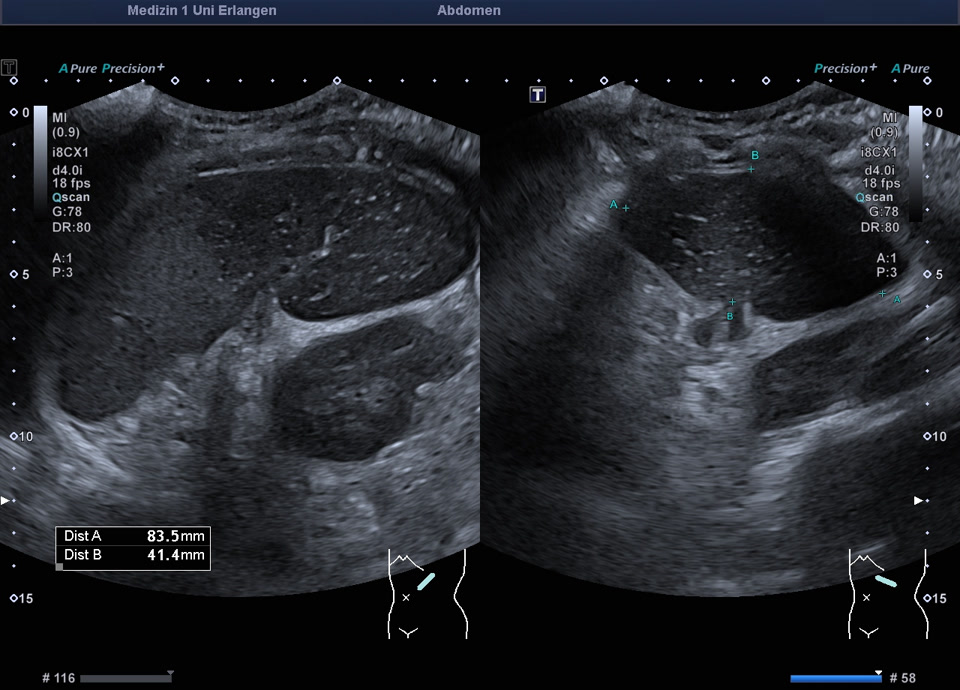

Epikrise: 19-jährige Patientin mit einem schweren angeborenen Herzfehler berichtet über plötzlich aufgetretene starke Schmerzen in der linken Flanke vor 14 Tagen. Sonographisch zeigt sich die Milz regelrecht lokalisiert, mit einem ausgedehnten Milzinfarkt der unteren Milzhälfte. Weder im Farbdoppler, noch im CEUS, lässt sich eine Restperfusion der unteren Milzhälfte feststellen. Therapeutisch wird eine Antikoagualtion begonnen und eine Verlaufskontrolle in 4 Wochen veranlasst.